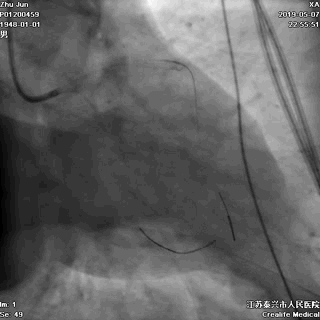

二、导丝到位

---筑牢生命线

导丝分别进回旋支和前降支

LAD和LCX,任一根血管都不能丢!这一步的价值,就相当于是构筑生命线。